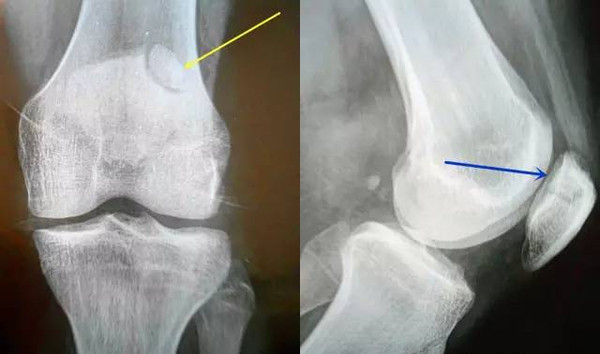

今天要为大家介绍的,是发生在膝关节髌骨,也叫波楞盖儿上的,貌似骨折的一种假骨折。也就是说,有部分人的髌骨本来就是裂开的两瓣,叫“二分髌骨”。这种二分髌骨,很多人是没有症状的,不去拍片子,本人可能永远都不会知道,因为你自己是摸不出来的。但是,有时候这种二分髌骨会引起膝关节的疼痛,叫“疼痛性二分髌骨”。

“疼痛性二分髌骨”就是今天的主角。故事往往是这样的:因为膝关节扭一下、磕一下而疼痛去就诊,本来是以为是软组织伤、半月板伤一类的,结果一拍片子——啊?髌骨裂开了?我怎么这么容易就骨折了?——我也的的确确见过有经验不足的低年资医生诊断成“髌骨骨折”的,打上石膏好长时间骨折也不长,最后发现是先天的二分髌骨!如果有因此而去做手术的,那就太悲剧了。

接下来,我们大家就一起来了解一下,这种颇具有迷惑性的“二分髌骨”。首先,从概念上讲,“二分髌骨(bipartite patella,BP) ”是部分人群在发育阶段由于某些因素的干扰出现的髌骨骨化异常——也就是发育过程中就没有像正常人群那样,长成一块完整的骨块,而是自然形成了两块。二分髌骨是一种解剖异常,一般都是没有症状的,而在剧烈活动、大运动量的体育训练后出现了疼痛不适,变成疼痛性二分髌骨( painful bipartite patella,PBP)。

Saupe教授,根据副髌骨一般出现的位置,将二分髌骨分为3型:I型骨化核位于髌骨下极;Ⅱ型位于髌骨外侧;Ⅲ型位于髌骨外上角,其中Ⅲ型最为多见。也就是说,分离的那小块髌骨很少会出现在髌骨的内侧,往往是出现在髌骨的下方,外侧或外上位置,尤其是外上部位。这对于我们通过X线判断二分髌骨有重要的参考意义。